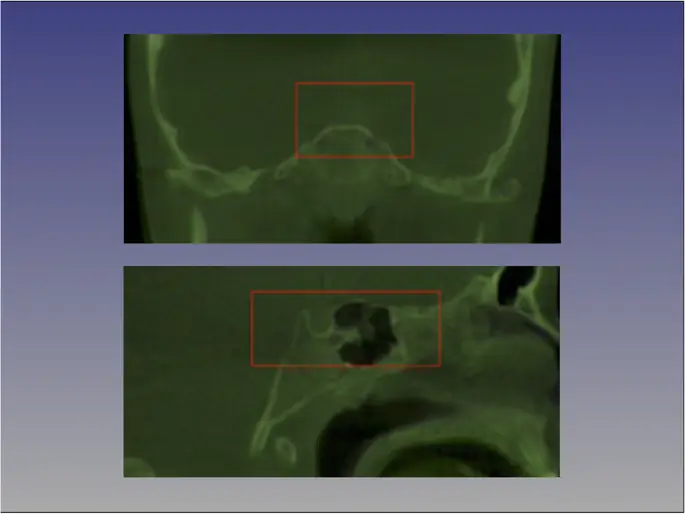

На основе вокселей - метод дельфинов

Для каждого пациента изображения КЛКТ Т1 и Т2 были аппроксимированы с использованием четырех ориентиров, расположенных на правом и левом фронтозигоматических швах, а также на правом и левом ментальных отверстиях, и наложены на основание черепа с помощью инструмента наложения вокселей в Dolphin 3D (Chatsworth, CA-версия) 11.8.06.15 премиум). Площадь основания черепа, используемого для наложения, определялась красной рамкой на трех разных многоплоскостных изображениях (осевом, сагиттальном и корональном). Наложение было достигнуто путем перемещения изображения T2 относительно изображения T1 с созданием зарегистрированного изображения T2. Процедура ориентации головы не была выполнена, поскольку программное обеспечение Dolphin не имеет инструмента.

figure8

Аппроксимация краниального основания методом Дельфина. Площадь основания черепа, используемого для наложения, определяется красной рамкой на трех разных многоплоскостных изображениях (осевом, сагиттальном и корональном), здесь показаны только срезы коронкового и сагиттального разрезов. Наложение достигается путем перемещения изображения T2 относительно изображения T1, создавая зарегистрированное изображение T2

Изображение в полном размере